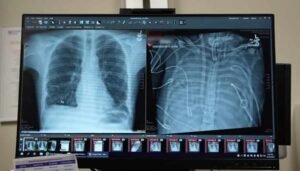

Los pacientes con fracturas de la columna vertebral causadas por tumores u osteoporosis generalmente se someten a un procedimiento llamado cifoplastia, donde la fractura se llena con cemento quirúrgico.

Si bien la cifoplastia puede estabilizar el hueso, a los pacientes de cáncer aún les quedan tumores de la columna vertebral que son muy difíciles de alcanzar con la quimioterapia convencional, que debe atravesar la barrera hematoencefálica cuando se administra por vía intravenosa.

Ahora, investigadores de la Universidad de Illinois en Chicago informan en la revista PLOS ONE , que al agregar partículas magnéticas al cemento quirúrgico que se usa para curar las fracturas de la columna vertebral , podrían guiar las nanopartículas magnéticas directamente a las lesiones cerca de las fracturas. Las nanopartículas unidas a varios medicamentos se han utilizado para dirigir medicamentos a ubicaciones específicas o tipos de células en el cuerpo. Más comúnmente, esto se logra uniendo una cantidad diminuta de medicamento a la nanopartícula, que está diseñada para unirse también a un tipo específico de célula, como una célula cancerosa.

Usando un modelo de cerdo para estudiar el sistema de administración de fármacos guiado magnéticamente , Denyer y sus colegas lograron dirigir con éxito las nanopartículas magnéticas hacia el cemento magnético en las vértebras de la columna vertebral del animal. En estudios futuros para probar la eficacia de esta técnica en el tratamiento de tumores de la columna vertebral, las nanopartículas magnéticas estarían unidas a pequeñas cantidades de medicamentos de quimioterapia.